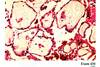

Patient likely died from what problem?

a) Cardiac arrest

Laminar Necrosis

Seen in hypoxic/ischemic injury